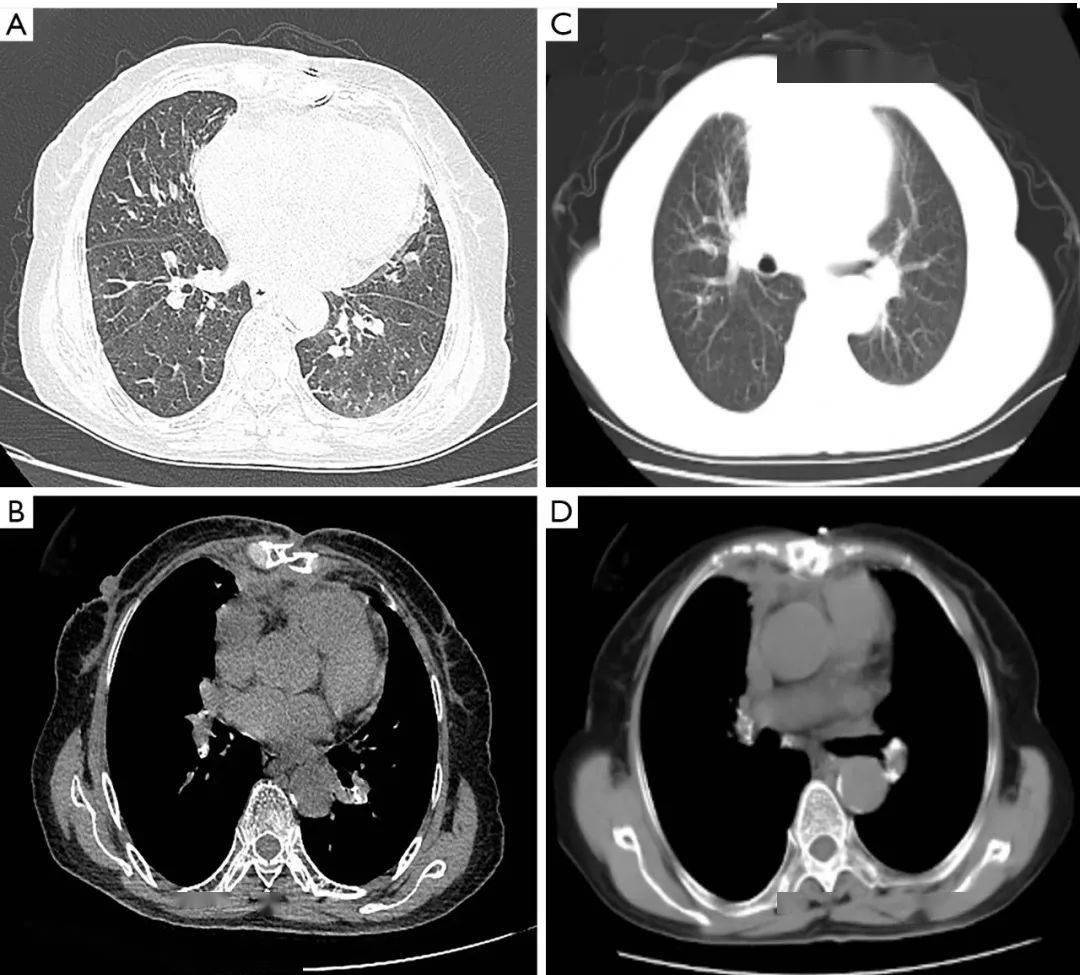

一例通过纵隔肿瘤切除诊断和治疗的心包间皮瘤病例|imdt 专栏_患者